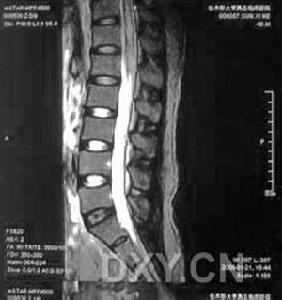

引發脫髓鞘疾病:其特徵的病理變化是神經纖維的髓鞘脫失而神經細胞相對保持完整。髓鞘的作用是保護神經元並使神經衝動在神經元上得到很快的傳遞,所以,髓鞘的脫失會使神經衝動的傳送受到影響。急性壞死出血性腦脊髓炎疾病的神經髓鞘可以再生,且速度較迅速,程度較完全,雖然再生的髓鞘較薄,但一般對功能恢復的影響不大。急性壞死出血性腦脊髓炎,由於反覆脫髓鞘與髓鞘的再生許旺細胞明顯增殖,神經可變粗,並有軸突喪失,因此功能恢復不完全。急性壞死出血性腦脊髓炎中出現頭痛的機率不高,但急性壞死出血性腦脊髓炎病人也有頭痛發作,歸納原因有兩方面:①神經的刺激性症狀,正常的神經纖維,感覺衝動發生於神經末梢和細胞體,運動衝動發生於細胞體;病變的神經纖維,衝動可發生於軸突的中部而向周圍和中樞傳導,這種異位衝動可以由易患性增高,對機械刺激非常敏感所致,也可是自發的緊隨著同一纖維的正常衝動後發生或某個刺激在病變部位引起反覆興奮,可造成疼痛。②急性壞死出血性腦脊髓炎的同時伴有淋巴細胞、漿細胞、多形核白細胞的浸潤,形成嚴重的炎性反應,刺激腦膜甚則引起顱內壓力增高而導致頭痛。 急性壞死出血性腦脊髓炎分成5類:①病毒性;免疫性;遺傳性(髓鞘形成不良);④中毒性/營養性;⑤創傷性。引發的脊髓炎性脫髓鞘性疾病目前認為是免疫介導性疾病,其臨床特點是:①患者均為兒童和青壯年;②急性起病,病前1個月常有感冒、發熱、感染、出疹、疫苗接種、受涼、分娩或手術史;③全面的神經查體往往能夠在脊髓症狀體徵外找到其它中樞神經系統受累的證據,如脊髓炎多合併視神經炎,脊髓型多發性硬化症常為多發病變;④腦脊液檢查寡克隆區帶陽性;⑤電生理和MRI可發現腦內一些亞臨床病灶,如誘發電位發現視神經、聽神經病變;MRI發現腦內白質異常信號。一些脊髓炎性脫髓鞘病變呈“假瘤樣”表現,其MRI表現出輕度占位效應,周圍有輕度水腫,可能有片狀出血信號,容易誤診為脊髓腫瘤。 內科藥物治療效果不佳。嗅鞘細胞移植為脫髓鞘疾病提供一條新途徑,可治療髓鞘破壞型疾病,包括多發性硬化、急性播散性腦脊髓炎、視神經脊髓炎以及放射性脊髓病。嗅鞘細胞移植治療脫髓鞘疾病的機理是利用嗅鞘細胞能促進神經軸索再髓鞘化的特性,促使脊髓修復,功能恢復。